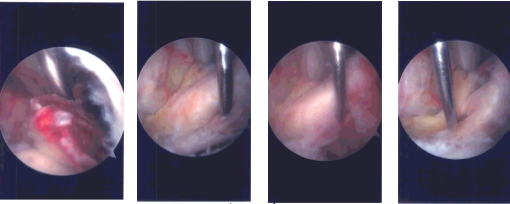

Intraoperative Arthroscopy Images 1

Intraoperative Arthroscopy Images

The tourniquet was elevated after exsanguinating the limb. Lateral entry portal was made. Arthroscope was inserted. Examination of the patellofemoral compartment showed no cartilage damage. Examination of the medial tibiofemoral compartment showed no meniscus or cartilage tear.

The Medical entry portal was made with the use of a spinal needle. Examination of the anterior patellar notch showed that avulsion of the ACL from the tibial attachment with raw bone. It was thoroughly irrigated and drained.

Examination of the lateral tibiofemoral compartment showed tearing of the anterior horn of the lateral meniscus in line with the ACL along with the intermeniscal ligament. It was decided not to repair the lateral meniscus because it was falling in line once the reduction of the ACL fragment was done.

The ACL fragment was reduced in its place and held with the use of a tibial tray. A #2 FiberTape was passed with the use of labral Scorpion through the posterior fibers of the distal ACL. This was followed by passage of a 1.3 mm Suture Tape in the same vicinity to achieve good hold on the ACL ligament.

The fragment was again held with the tibial ACL ring and a Beath pin was passed through the separate incision distally from the tibia into the knee joint. The sleeve was removed, but the ACL ring was kept in place to keep the fragment in place. A 4-mm cannulated drill was passed over the Beath pin and the Beath pin was removed.

Now, suture passer was passed through the cannulated drill and the cannulated drill was removed. The four tails of the sutures were noted on to the suture retrieval lasso and passed out of the tunnel. Once they were out, a good reduction of the ACL could be seen. There was no laxity of ACL.

All the four tails of the suture were put into the tibia with the use of 4.75 SwiveLock after drilling and tapping. A good reduction was achieved Final picture was taken and saved.